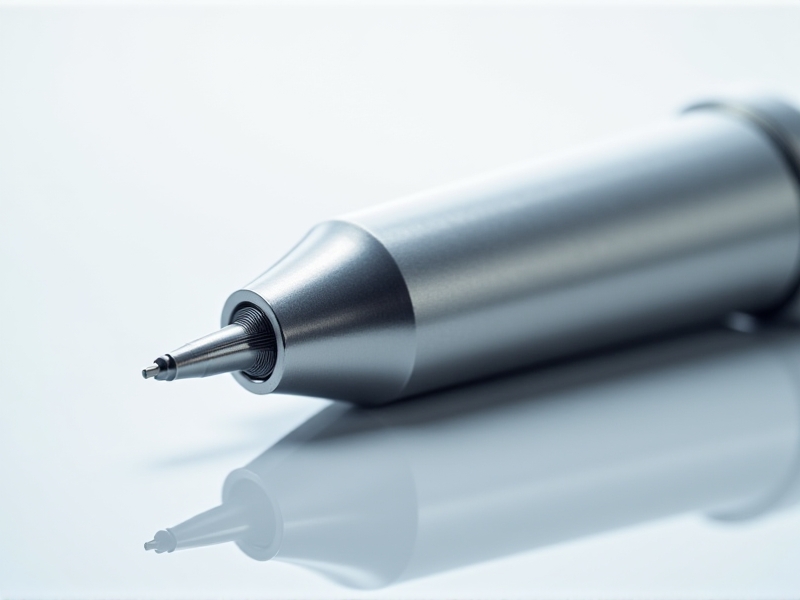

Transnasal cryotherapy is a non-invasive treatment that involves the application of cold temperatures to the nasal passages. The concept is based on the idea that cooling the trigeminal nerve, which is responsible for transmitting pain signals from the face to the brain, can help alleviate migraine symptoms. The therapy is typically administered using a specialized device that delivers a controlled stream of cold air or a cryogenic substance directly to the nasal cavity.

The procedure is quick, usually lasting only a few minutes, and can be performed in a clinical setting or at home with a portable device. The cold temperature is believed to reduce inflammation and constrict blood vessels, thereby reducing the intensity of migraine pain. Additionally, the therapy may help to modulate the activity of the trigeminal nerve, preventing the cascade of events that lead to a full-blown migraine attack.

As research into transnasal cryotherapy continues, there is potential for further innovations in migraine treatment. Advances in device technology may lead to more effective and user-friendly cryotherapy devices, making the therapy accessible to a broader range of patients. Additionally, ongoing studies are exploring the use of transnasal cryotherapy for other types of headaches and neurological conditions, expanding its potential applications.